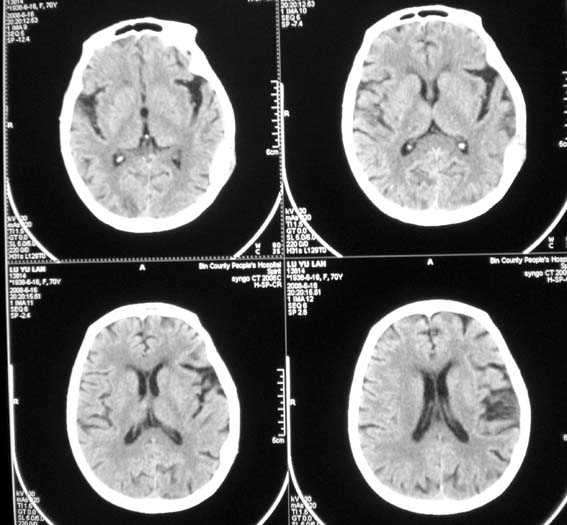

女,70岁,双肺结核,头痛,肿胀包块半年余,逐渐增大。

溶骨性破坏,未见明确死骨;病灶边缘不整,我考虑为颅骨转移瘤可能性大。建议仔细询问病史,积极寻找原发病灶。肺部如果扫描,最好请一并上传。

ct14067:颅骨破坏结果,转移瘤!

肝脏ct示肝癌,颅骨为转移所致!